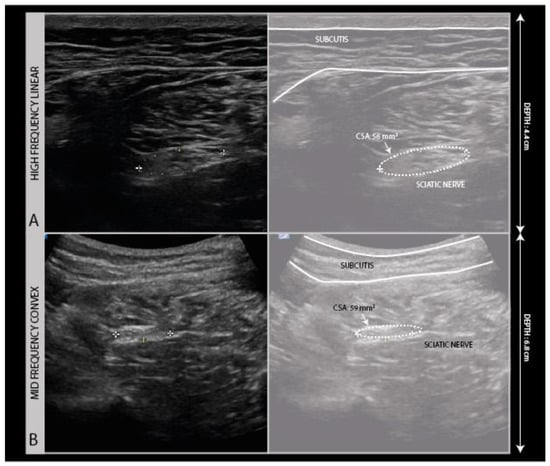

To create an ultrasound image, a high-frequency linear transducer in the 12–24 MHz range is used with a musculoskeletal ultrasound preset. For deep nerve segments, such as the sciatic nerve in the thigh and buttock region, it can be necessary to use a lower frequency (2–9 MHz range) probe with a convex surface to be able to get a view of the nerve (Figure 2).

Figure 2.

High frequency (5–16 MHz) probe image (A) compared to the low frequency (2–9 MHz) convex probe image (B) of a sciatic nerve traction injury following hip replacement surgery.